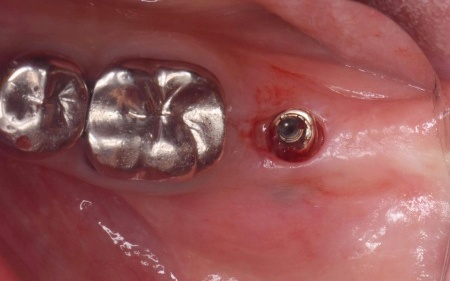

経過観察後、骨の状態が安定したことを確認したら、インプラント体(人工歯根)を顎の骨に埋め込む手術を行います。

インプラント体には、骨と結合しやすく体への親和性が高いチタン製のものを使用しました。

手術では、歯茎を切開した骨を露出させ、専用の器具で慎重に穴を形成したうえでインプラント体を埋入します。続いて歯茎を縫合し、インプラント体が骨と結合するまでの期間を設けました。

インプラントの埋入設計をしました。

インプラント体と骨の結合を確認しました。